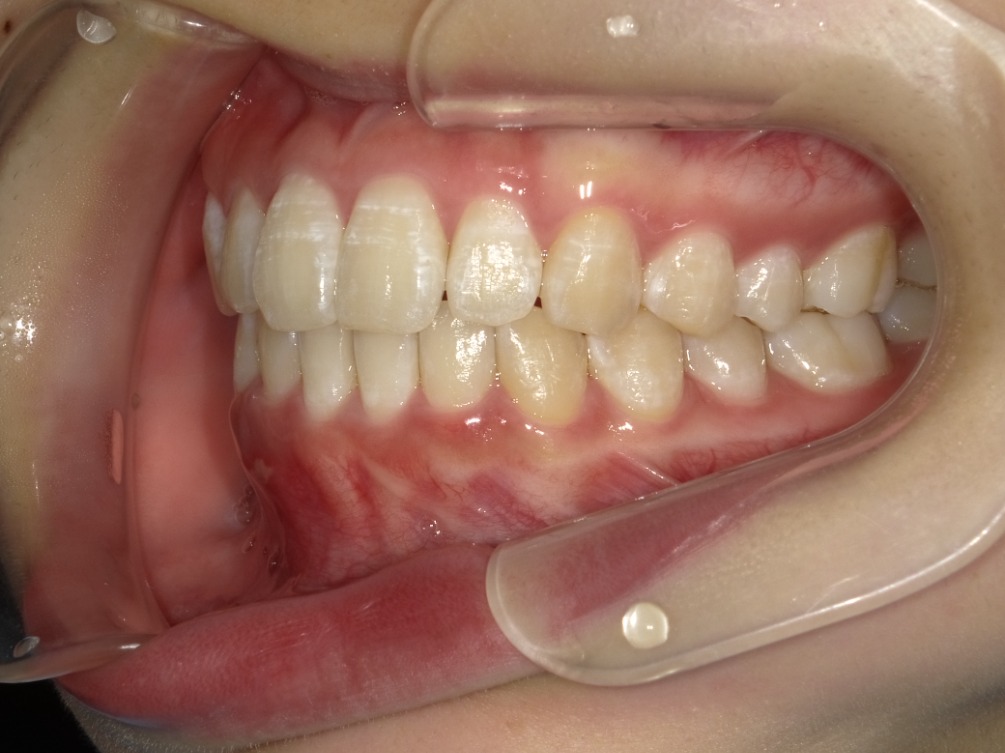

• BEFORE

症例集 インビザライン 右横

矢印

AFTER

右横